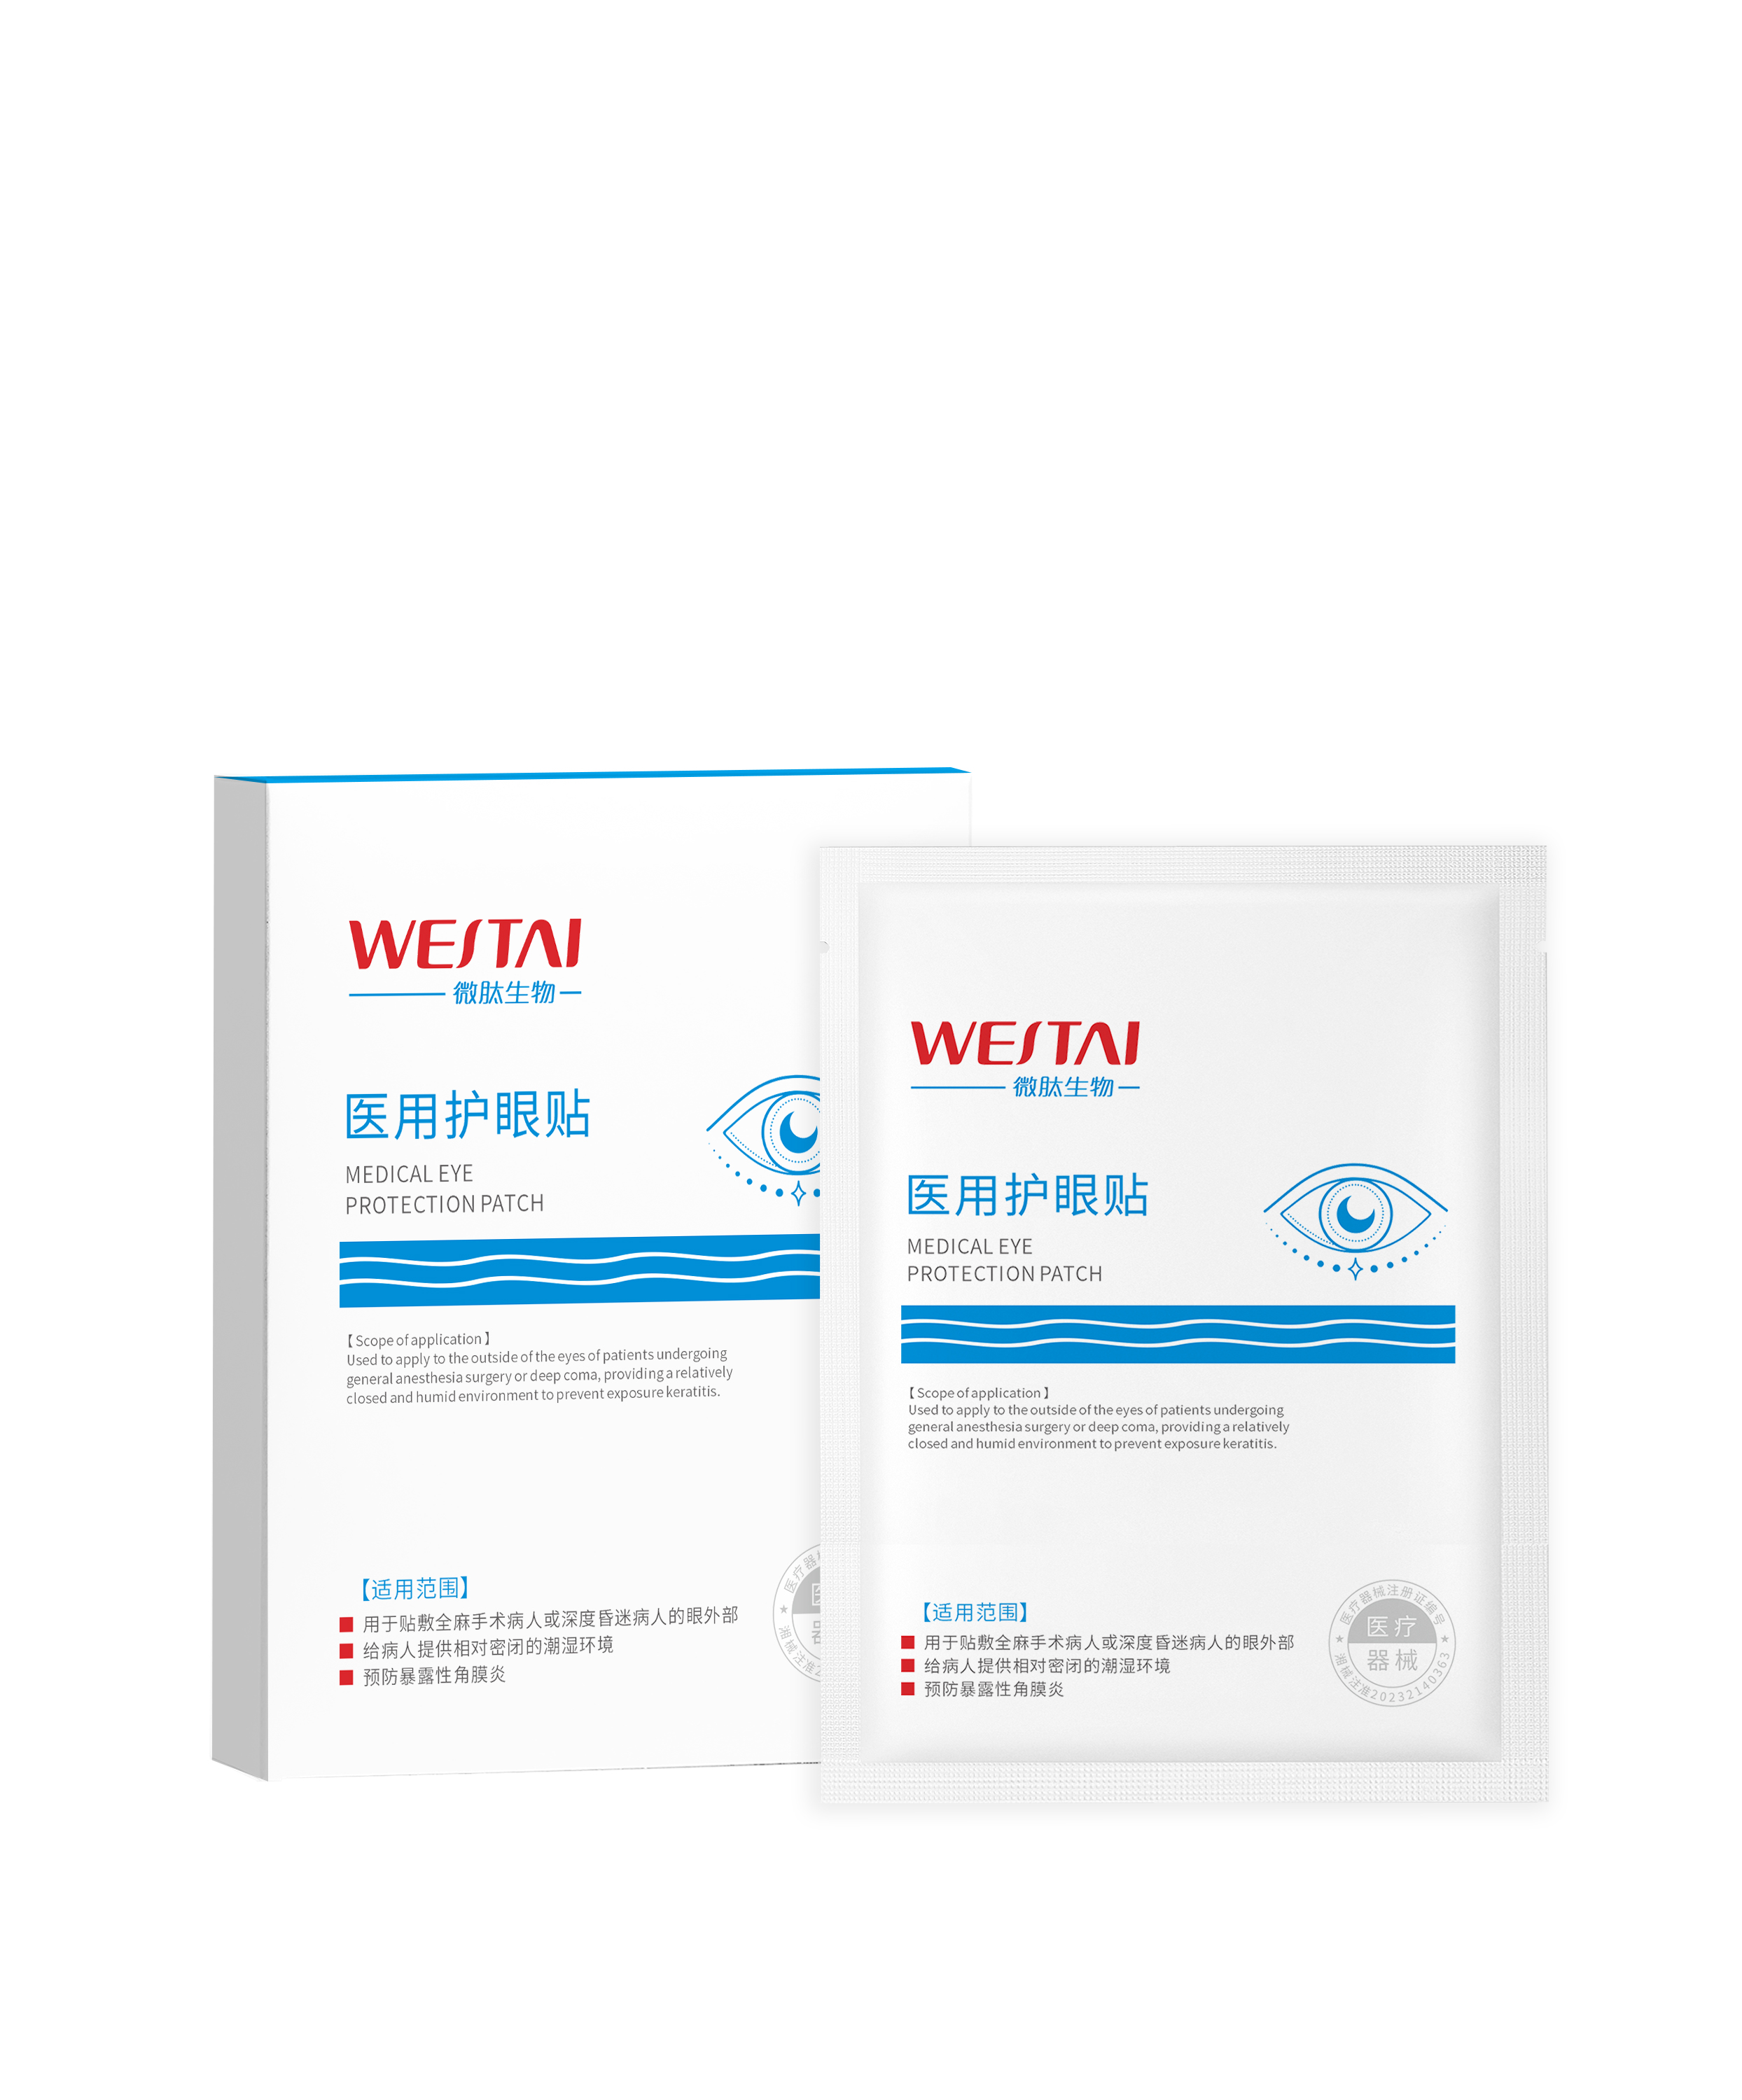

湖南微肽生物 | 【二类医疗器械】医用护眼贴,呵护健康新“视”界

时间:2024-11-27湖南微肽生物医药有限公司——械二类医用护眼贴 在现代社会,长时间使用电子设备已成为常态,这无疑增加了眼睛疲劳和干涩等问题的风险。湖南微肽生物医药有限公司推出的医用护眼贴,正是为了应对这些挑战而生。以下是关于这款产品的详细介绍: 产品特点 1. 舒缓眼部疲劳:湖南微肽生物医药的医用护…查看全文